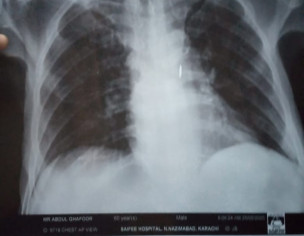

Patient was admitted in hospital due to cancer illness. He didnt have any fever or cough. The doctors performed chest X ray and determined on basis of X ray that patient has contracted coronavirus. I have attached the pictures of the X ray. Please verify if lungs are clear or not.

If they are suspecting corona ask them to do PCR test. X-ray chest is not specific for Covid. CT chest with contrast will clear the quirey

not necessary that all the patients of cancer have covid 19 but now a days it is nesccery to perform covid test of every immnocompromiz pt. Cancer is one of them . X ray chest is not normal but i m not an xray specialist. All the immunocompromised are nesccery to perform this test and indications to take precautions for doctos . If the test is positive than inform the relatives.